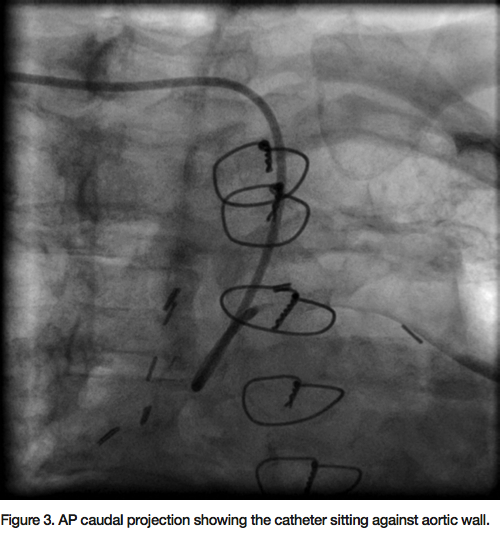

90% eccentric focal stenosis in the distal portion of the vein graft, very close to the anastomosis (Figure 2). Weight-based bivalirudin was initiated and a 6 Fr AL1 guide was used to cannulate the SVG to LAD. Though the severe tortuosity caused the cannulation of the graft to be challenging, a very co-axial supportive guide position was achieved (Figure 3, Figure 5). The lesion was crossed with a Kinetix wire (Boston Scientific). Due to the proximity of the lesion to the anastomosis, no distal protection device was deployed. A 3.5mm x 12mm Resolute drug eluting